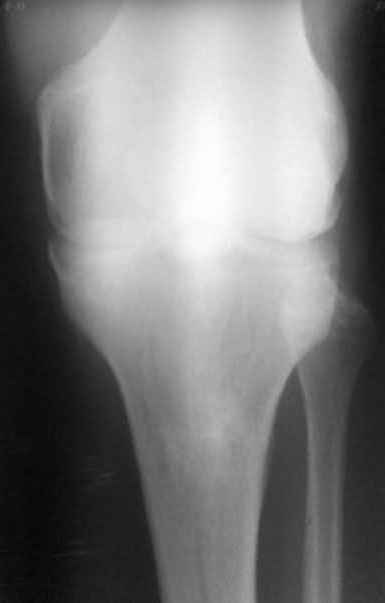

Уважаемый доктор Зайцев! Причина деформации проксимальной тибии у Вашего пациента - преждевременное и несимметричное закрытие зоны роста передней части проксимальной ростковой зоны б/б кости в следствии окультной травмы произошедшей в возрате 10-12 лет. Есть 2 причины рекурвационной деформации в области коленного сустава - мягкотканевая и костная.В данном случае Вы имеете дело не с рукурвацией коленного сустава, а с рекурвационной деформацией проксимальной голени. "Заднего выдвижного положения" на самом деле нет.То, что Вы видите на боковом снимке - это не задний подвывих голени - это снимок, сделанный в сгибании коленного сустава. Дело в том, что костные дефорсации в области коленного хорошо компенсируются за счёт движения в суставе. поэтому то, что вы видите, как задний подвывих на самом деле - сгибательное положение колена.

пациент наконец то объявился вновь и мы смогли выполнить новые снимки как лежа так и в нагрузке

если у вас остались силы, давайте обсудим